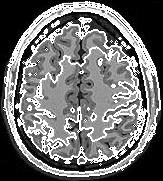

Segmentation of an MRI brain image, using two level set functions to represent the evolving contours